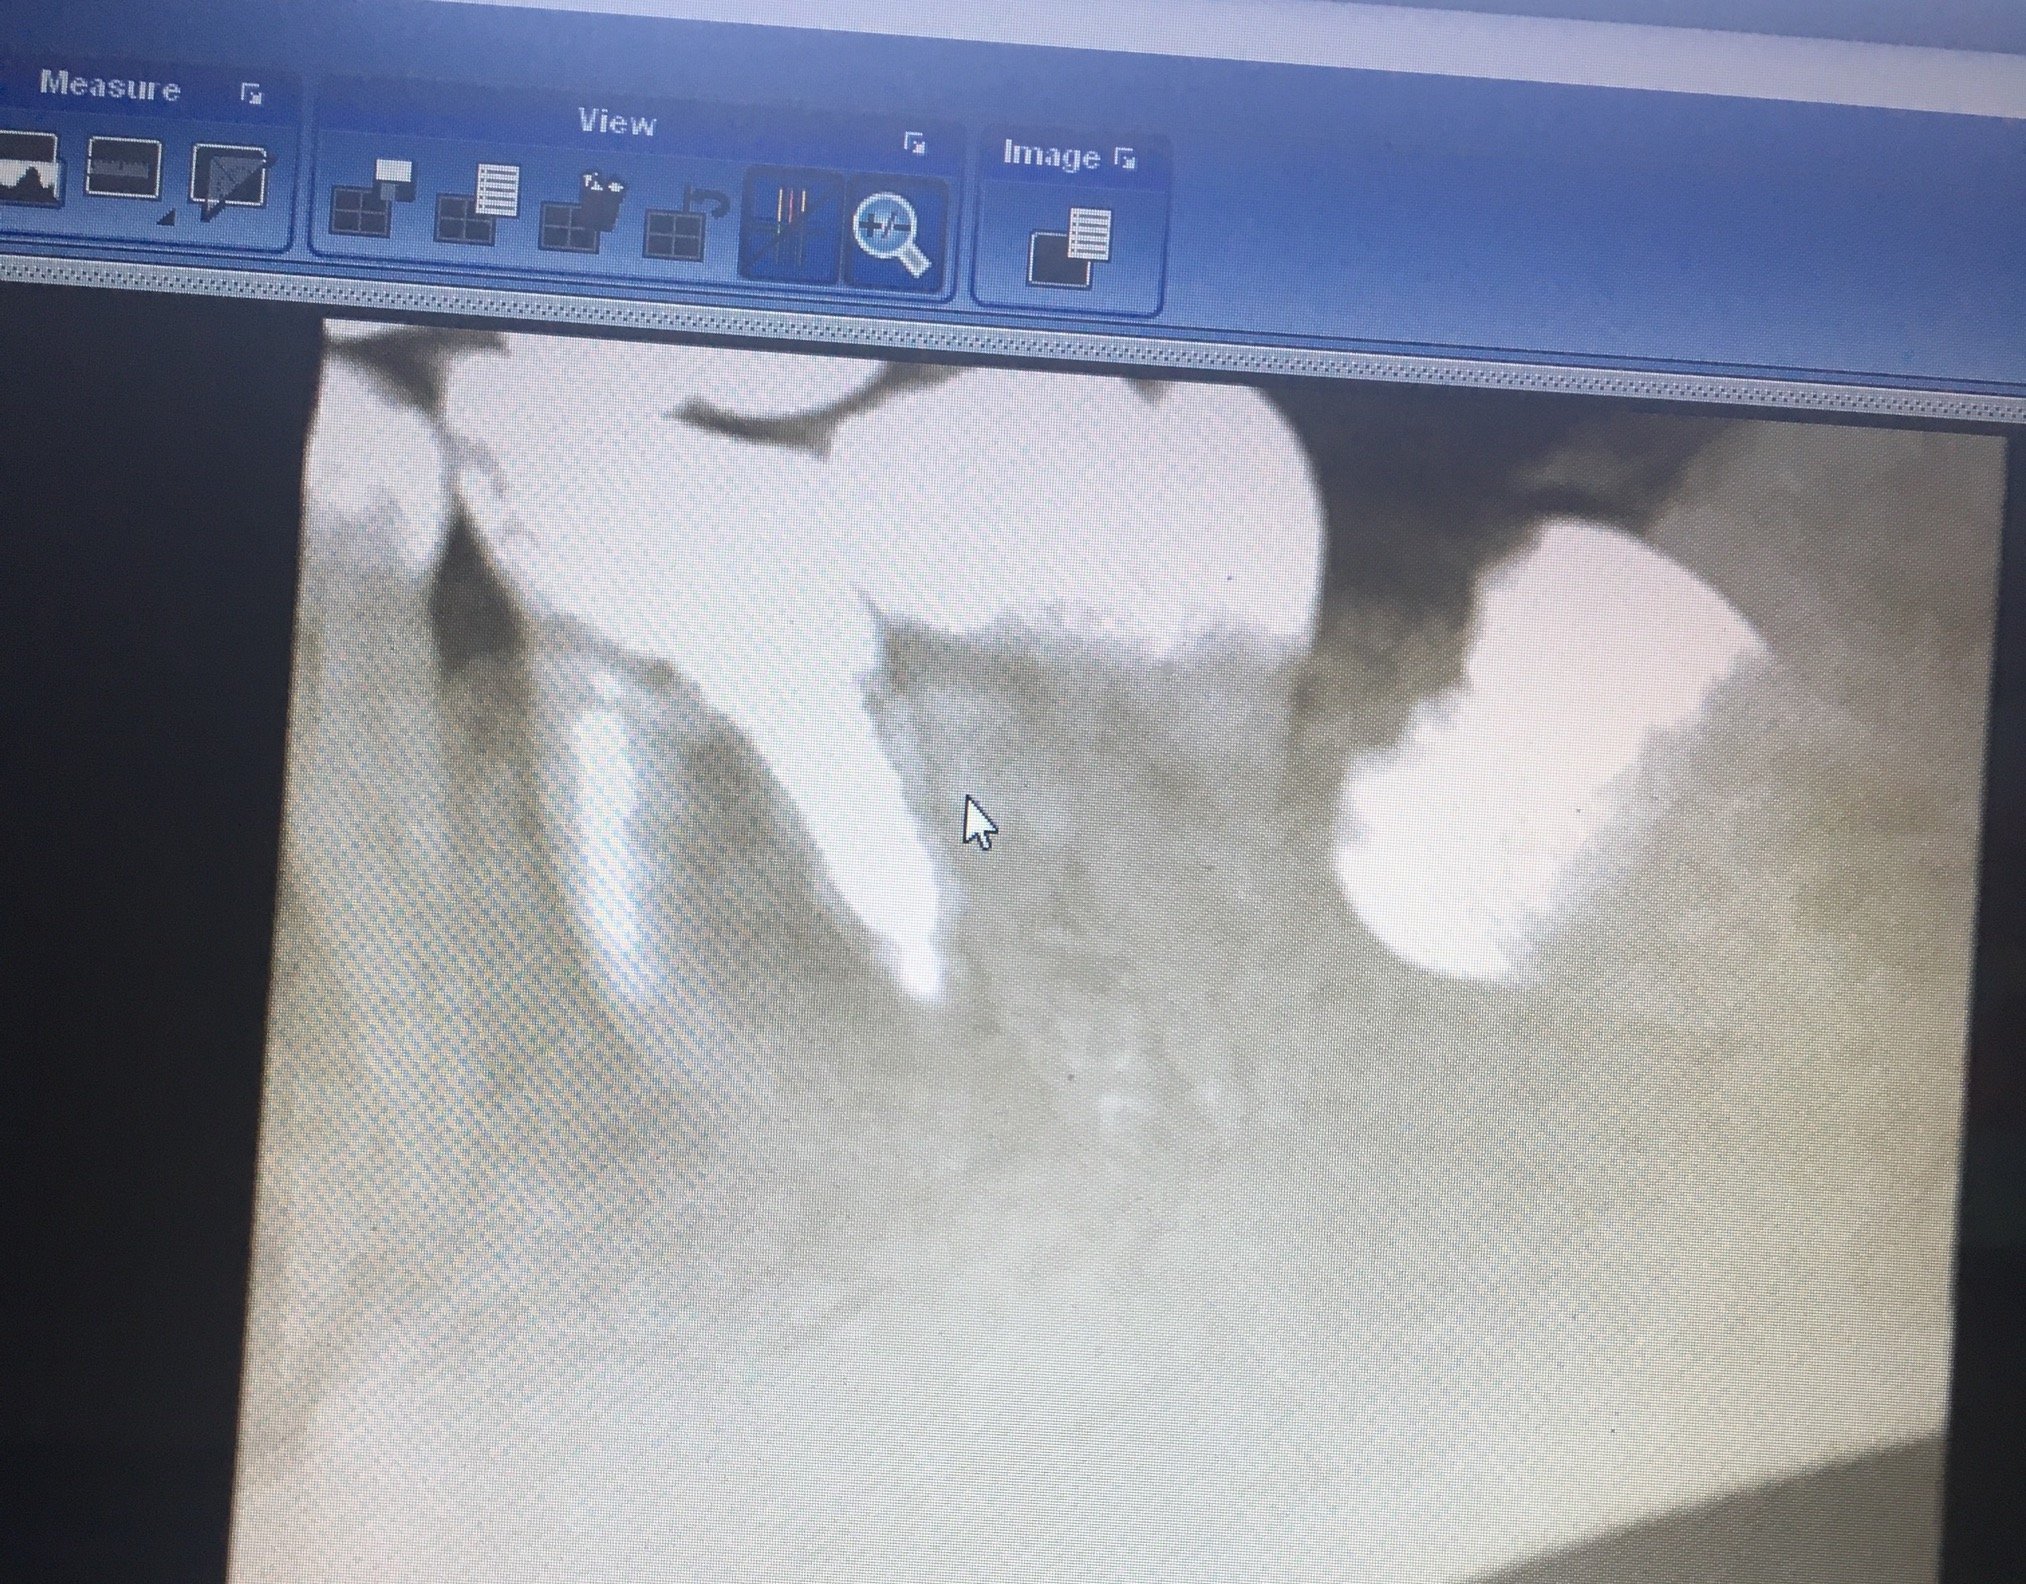

Какво се случва с кореновия канал, ако пълнежът излезе извън него?

Ако пълнежът излезе извън коренови канал, това може да създаде проблеми. Излизането на пълнежа може да доведе до инфекция или реинфекция на зъба. В такъв случай е необходимо да се консултирате със зъболекар, който може да прецени дали е необходимо повторно лечение на кореновите канали или други процедури за спасяване на зъба.